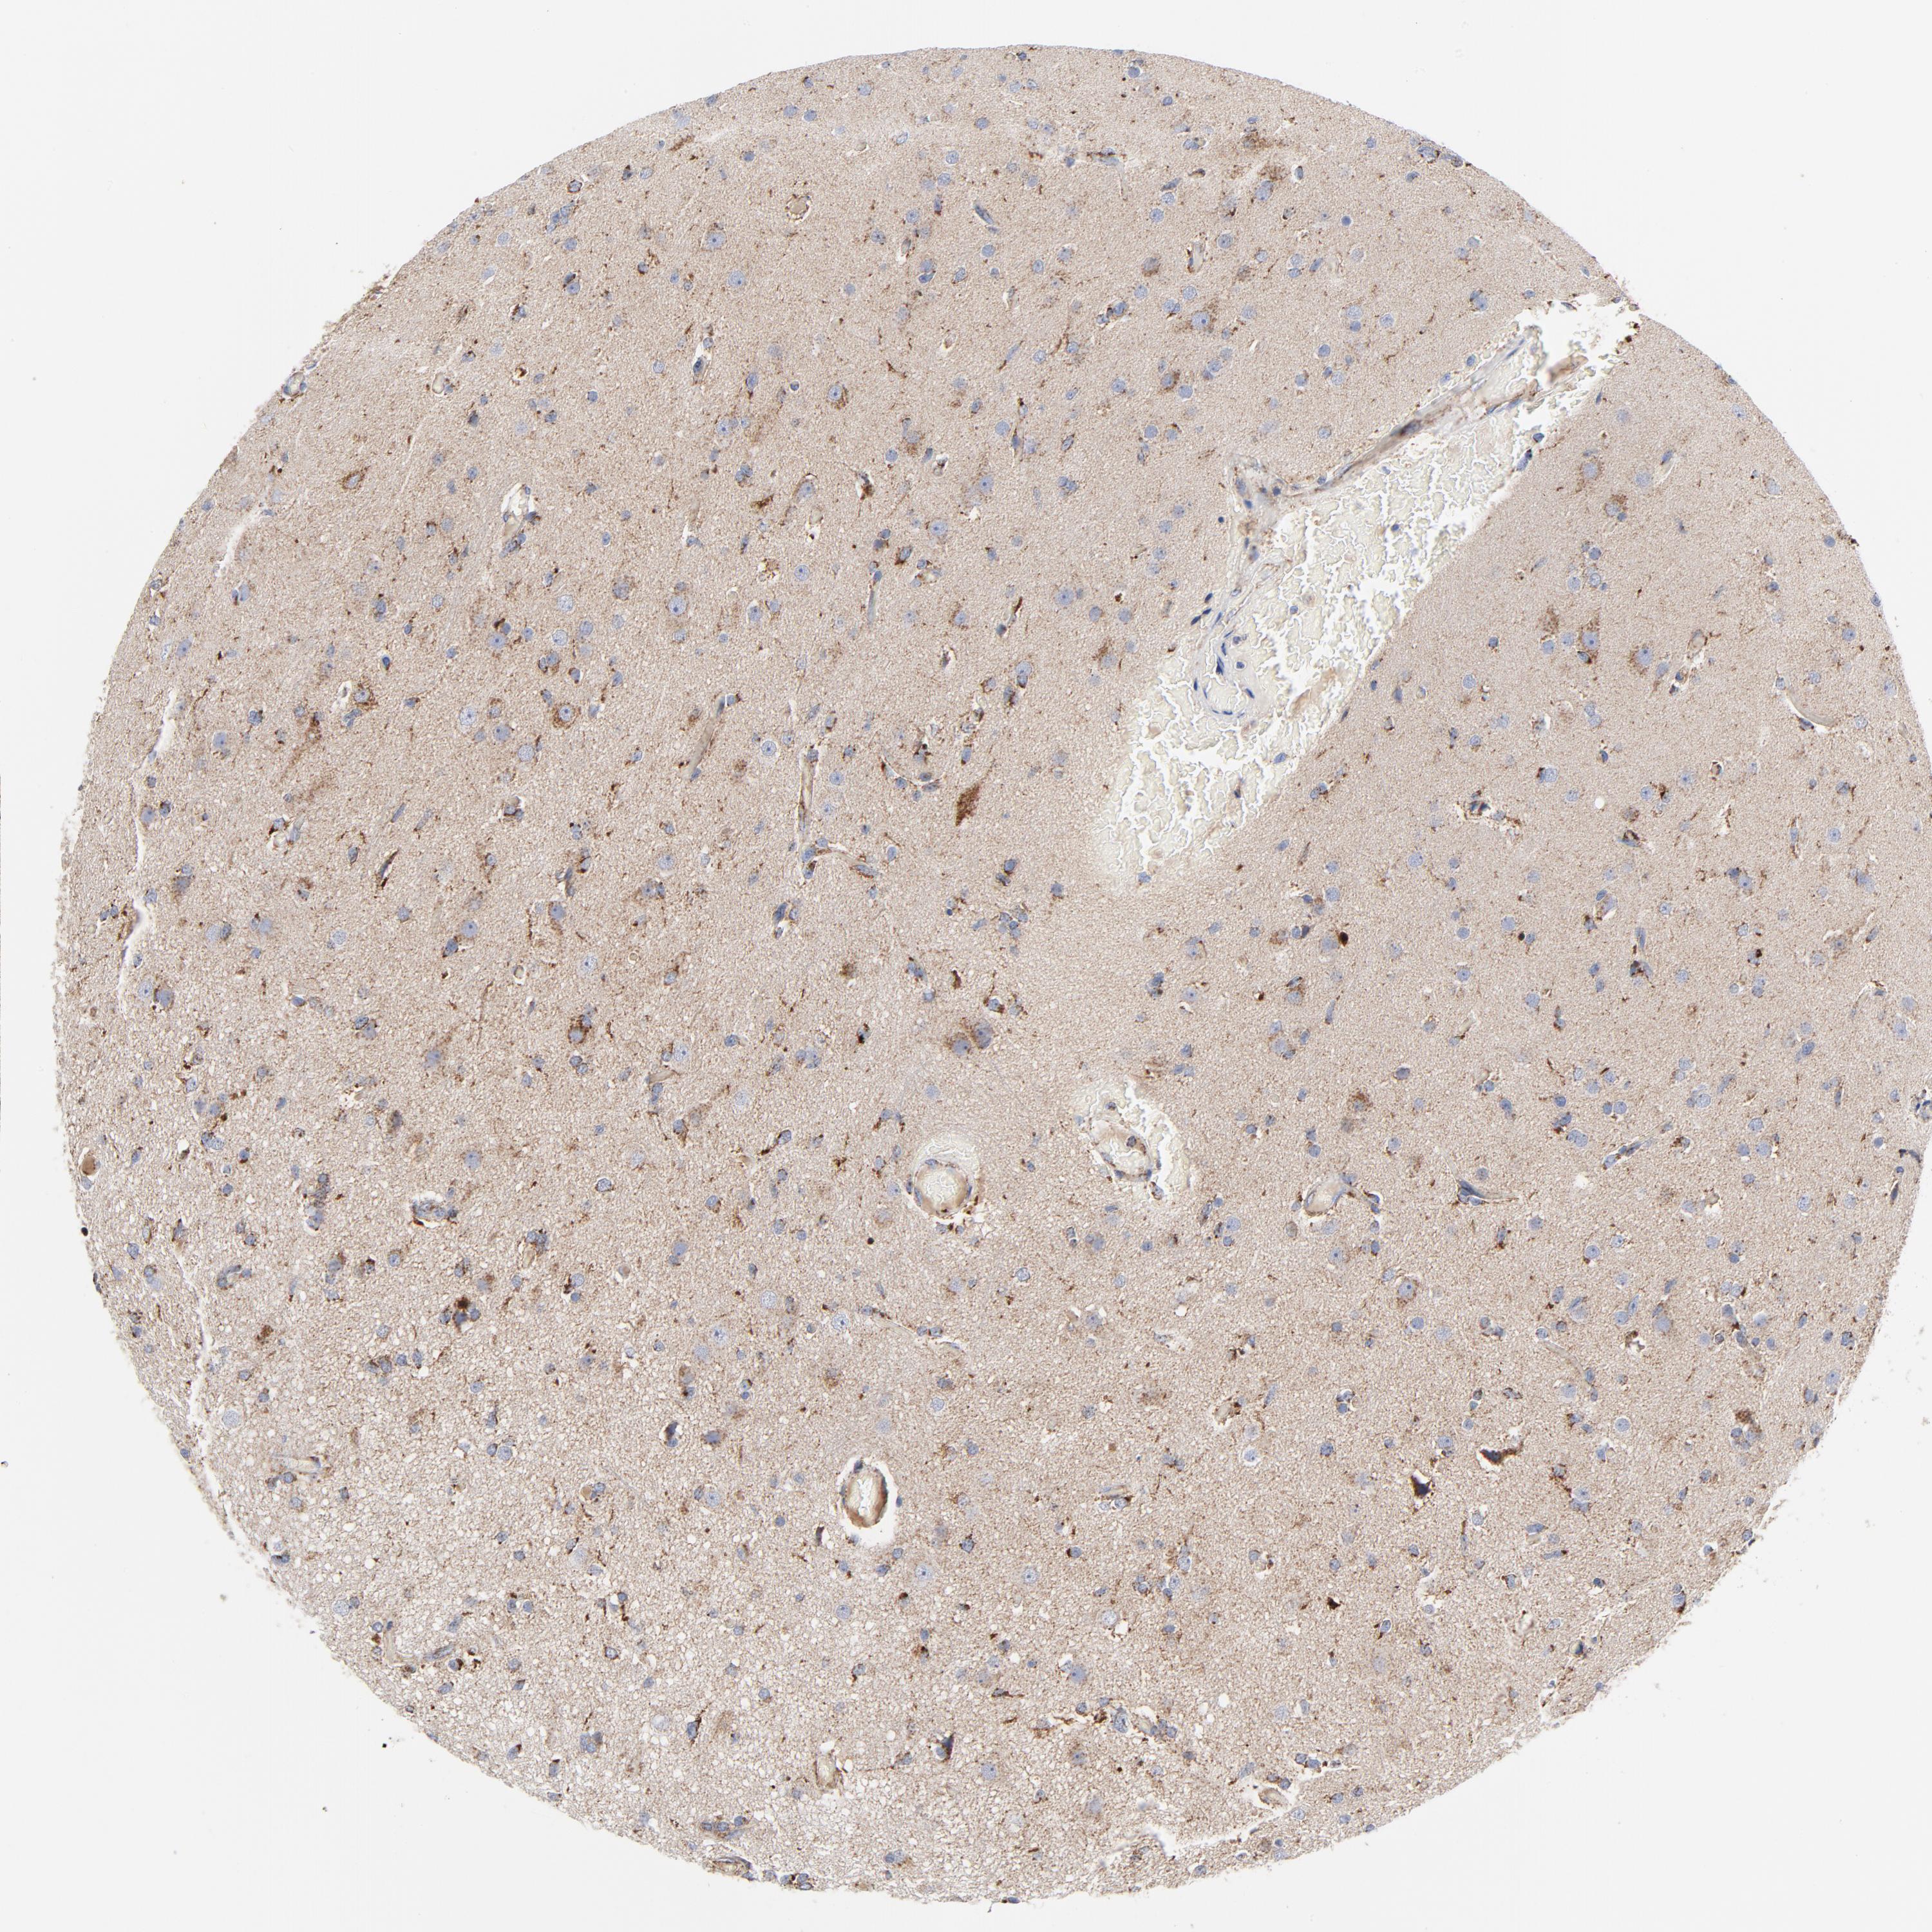

GLIOMA - Protein expressioni

A mouse-over function shows sample information and annotation data. Click on an image to view it in a full screen mode. Samples can be filtered based on level of antibody staining by selecting one or several of the following categories: high, medium, low and not detected. The assay and annotation is described here.

Note that samples used for immunohistochemistry by the Human Protein Atlas do not correspond to samples in the TCGA dataset.

Antibody stainingi

Antibody staining in the annotated cell types in the current human tissue is reported as not detected, low, medium, or high, based on conventional immunohistochemistry profiling in selected tissues. This score is based on the combination of the staining intensity and fraction of stained cells.

Each image is clickable and will lead to virtual microscopy that enables deeper exploration of all samples and also displays staining intensity scores, fraction scores and subcellular localization as well as patient and tissue information for each sample.

Antibody HPA001825

Antibody CAB003857

Staining

High

Medium

Low

Not detected

Intensity

Strong

Moderate

Weak

Negative

Quantity

>75%

75%-25%

<25%

None

Location

Nuclear

Cytoplasmic/membranous

Cytoplasmic/membranous,nuclear

Glioma, malignant, High grade

Glioma, malignant, Low grade

Glioma, malignant, NOS